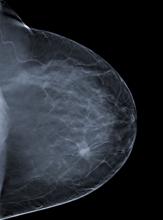

Women whose breast cancer has spread to just a few lymph nodes under their arm are less likely to have their disease recur or to die from it if they have radiotherapy after mastectomy, according to new research to be presented at the European Breast Cancer Conference (EBCC-9) and published in The Lancet.

The global burden of breast cancer remains immense in 2013, with over 1.6 million new cases being diagnosed annually.